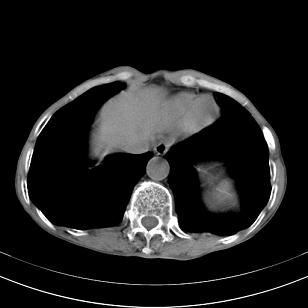

标题: 男,65岁,反复右上腹痛, [打印本页]

标题: 男,65岁,反复右上腹痛,

胃镜提示十二指肠占位